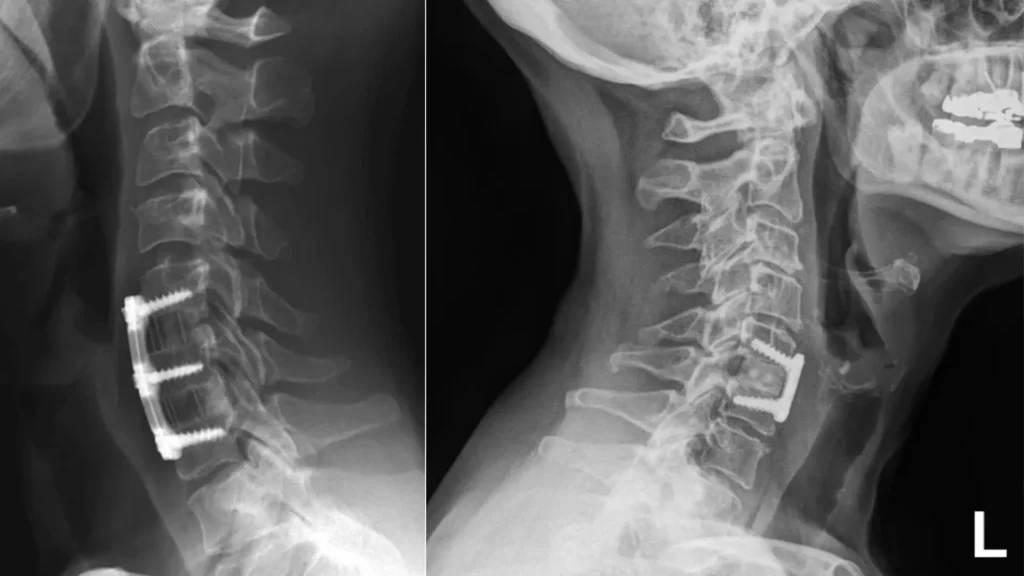

There are many different surgical approaches to treat back pain or sciatica. Some of these procedures may cause significant trauma to surrounding tissues or require fixation with hardware. Other procedures may only require a small incision with minimal trauma to surrounding tissues.

Lumbar discectomy surgery is performed whenever a herniated disc is pinching nerves in your back. Some doctors prefer to use an open approach when performing lumbar discectomy. This requires a large incision and dissection of your back muscles.

Other neurosurgeons use a minimally invasive approach to lumbar discectomy. This procedure uses a tiny incision with sparing of your back muscles. Your doctor will use specialized tools to remove the disc material that is pinching your nerves and causing your pain.

Both surgeries achieve the same goal-to relieve pressure from your spinal nerves. However, the minimally invasive approach may hasten your lumbar discectomy recovery time.